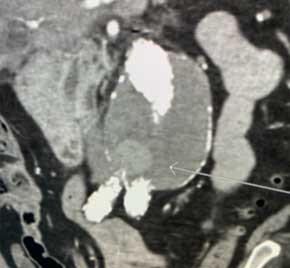

Type II Endoleak embolized with Embold Fibered Coils​

Scan of vein before placement of coil. Visualizing the pulmonary artery​

Scan of vein after Embold fibered coil. After Embold Fibered placement​

Anand Joshi, MD​

Grant Medical Center​

Columbus, OH​